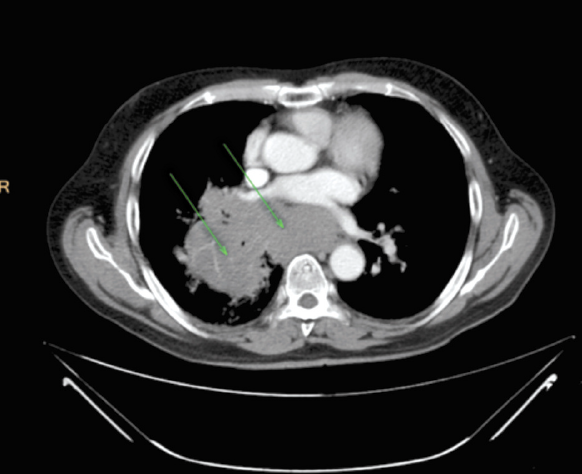

При контрольном обследовании в ноябре 2019 г. (рис. 2) отмечена положительная динамика: уменьшение размеров таргетных очагов до 85×90×100 мм и 54×56×100 мм, новых очагов не обнаружено.

Рис. 2. Пациент 1934 г. р. МСКТ органов грудной клетки с внутривенным контрастированием, ноябрь 2019 г. (через 2 года после начала терапии).

Fig. 2. The patient, born 1934. MSCT of the chest cavity with contrast, November 2019 (two years after the beginning of the therapy).